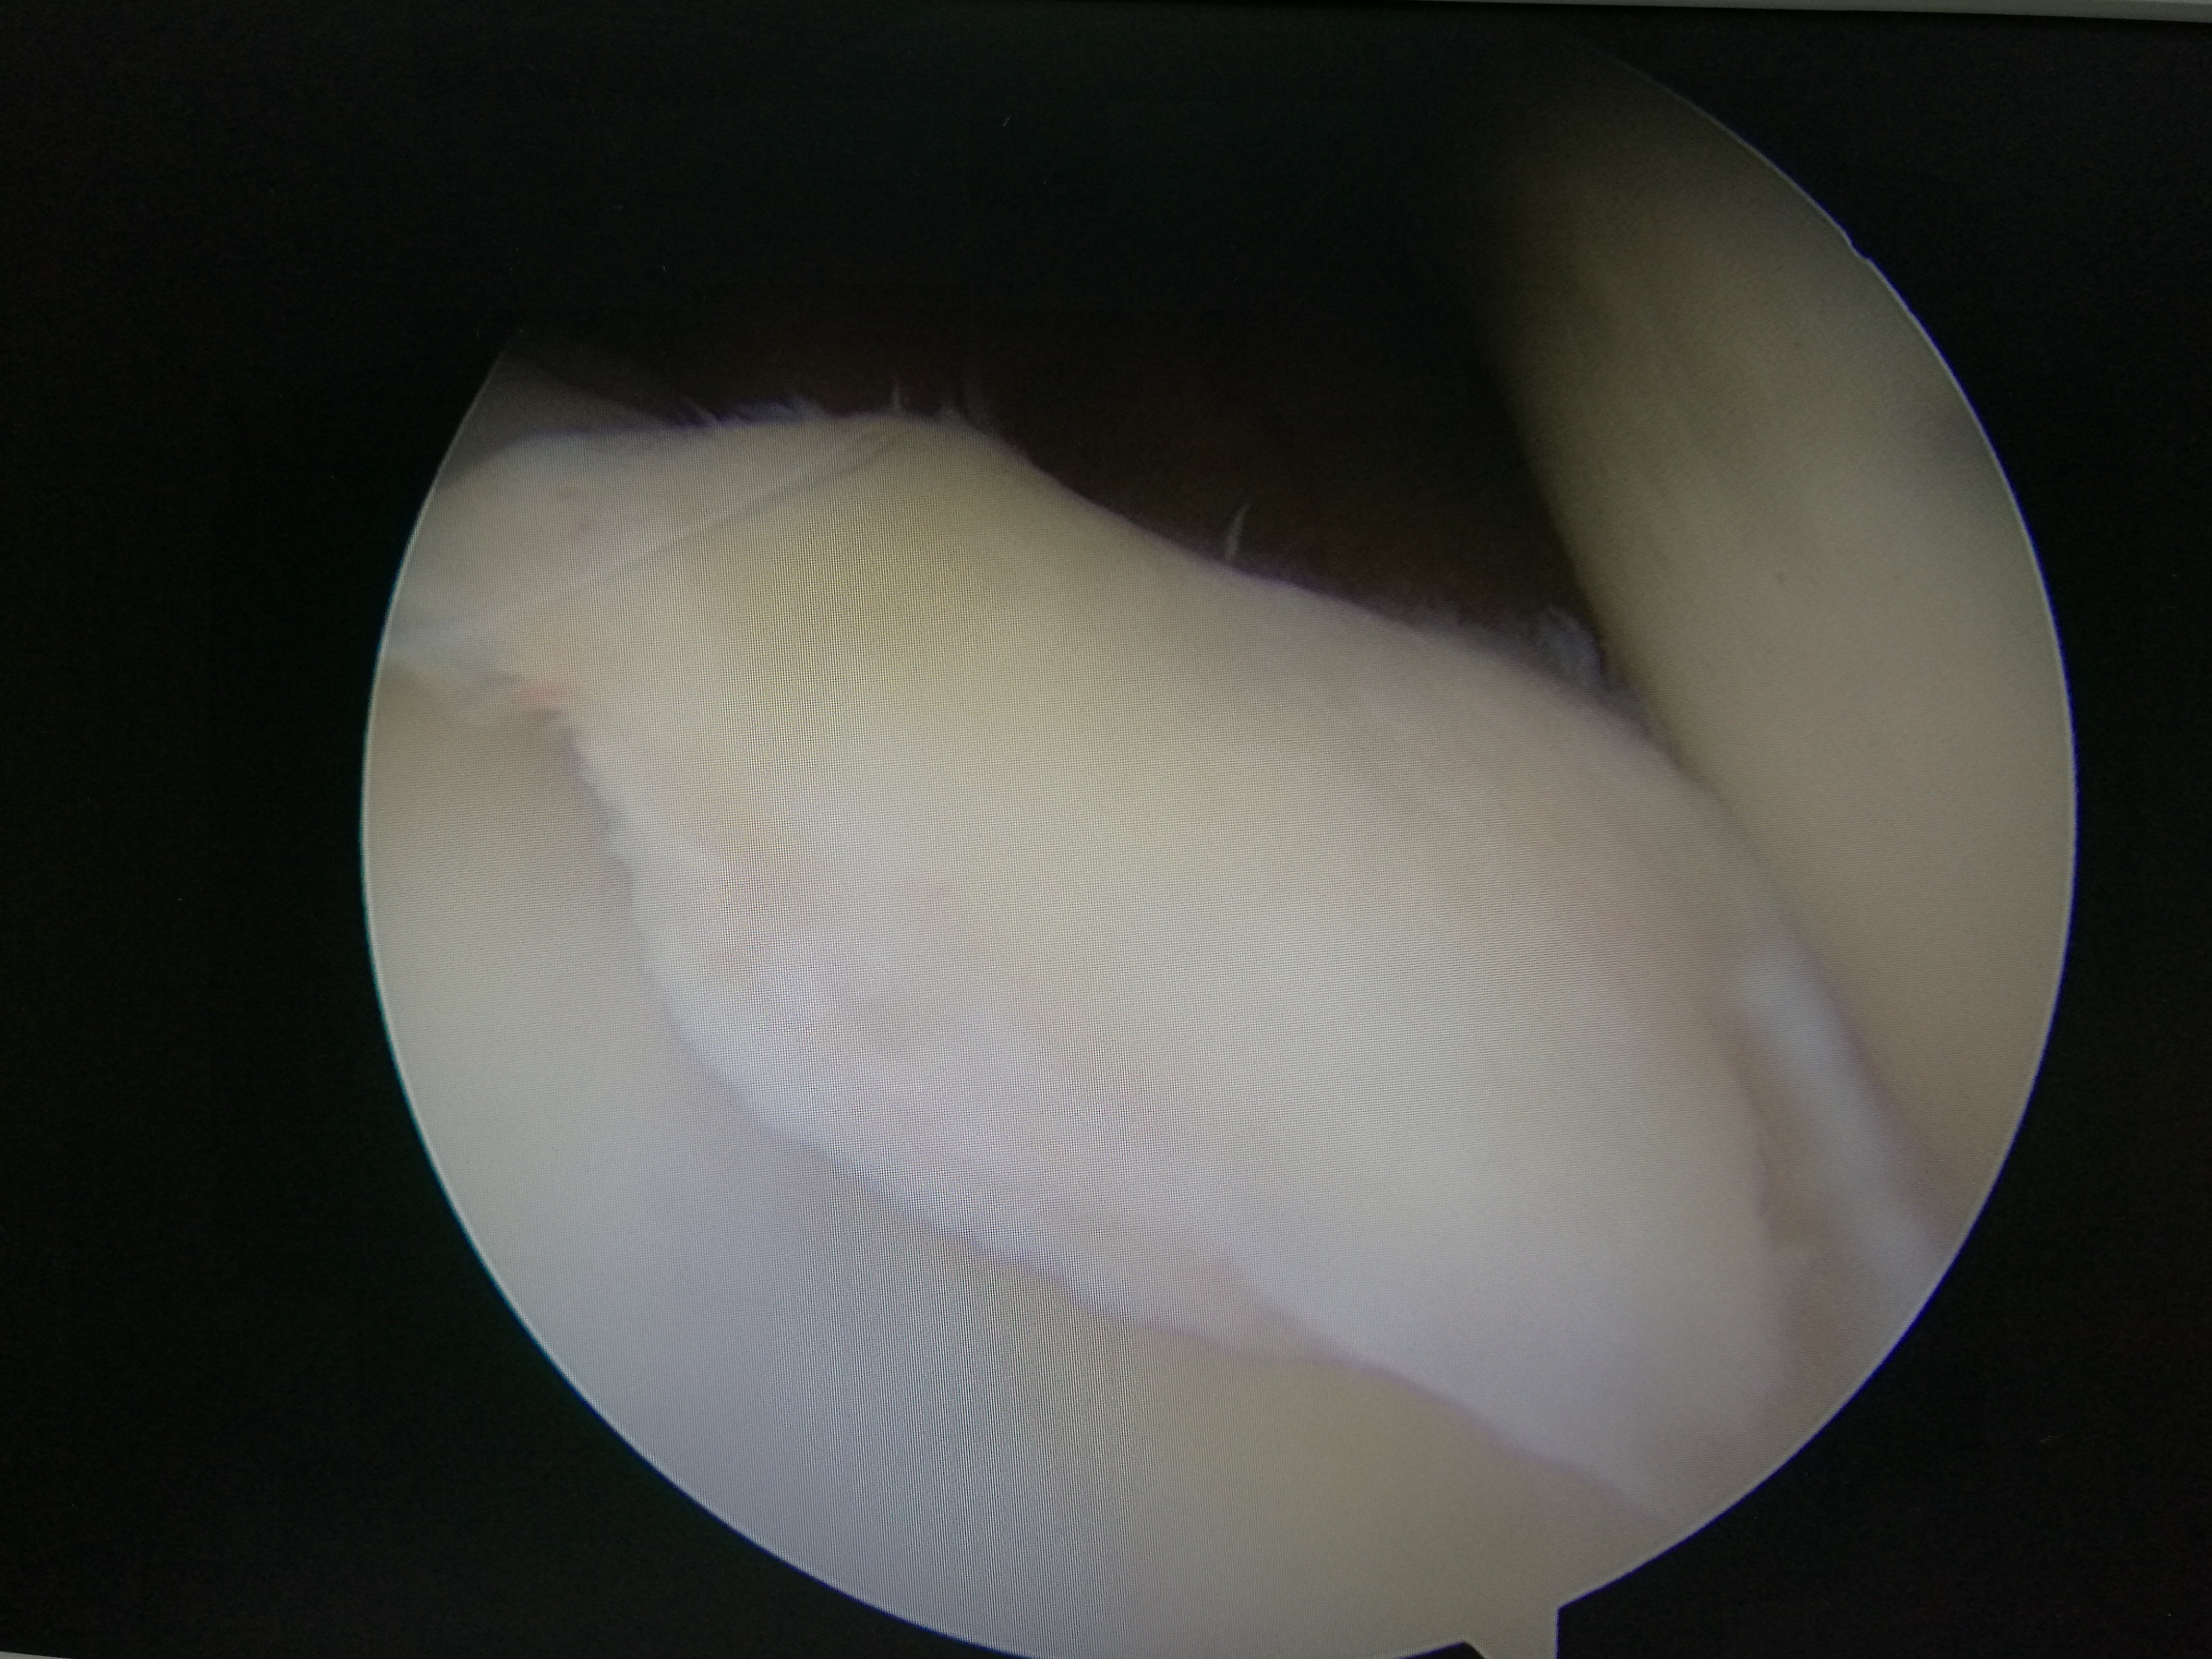

镜下手术图片,展示人体关节镜下情况:

骨科中心近两年共收治关节镜手术病人500余人,本人在近半年共收治关节疾病患者70余人,包括肩关节脱位及盂唇损伤、半月板损伤、交叉韧带损伤、叉韧带止点撕脱、髌骨脱位、色素性滑膜炎、关节游离体、老年骨性关节炎、踝关节外侧副韧带损伤伴距骨软骨损伤等。均通过关节镜或辅助关节镜手术治疗,短期内随访效果好,总体满意率在95%以上。